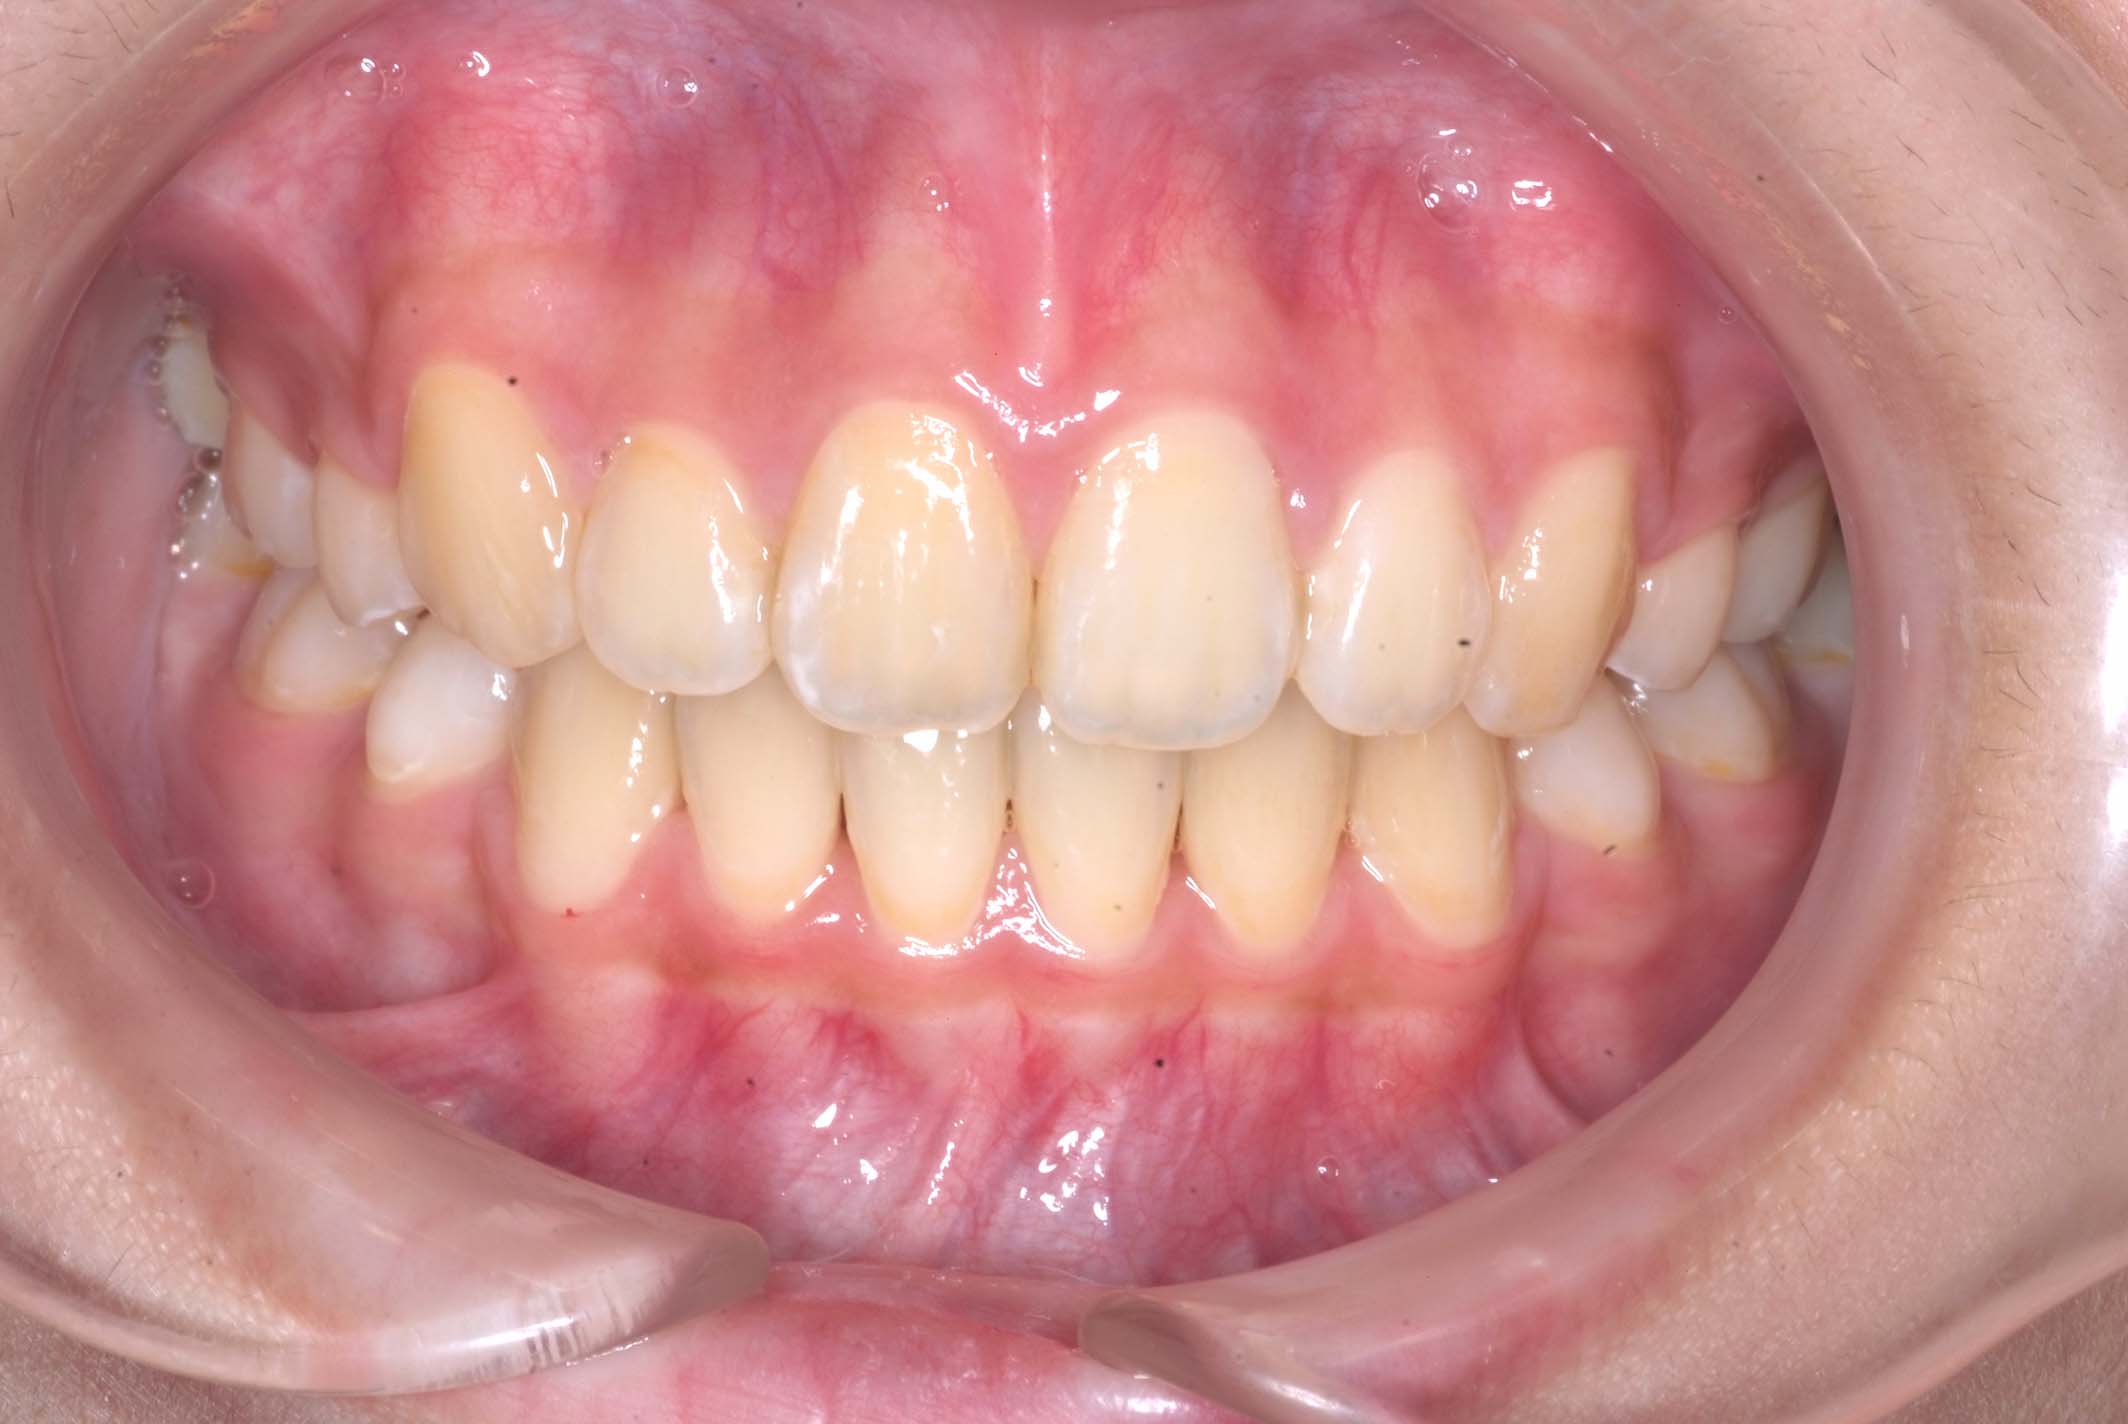

初診時年齢8才の女子で、前歯部開咬を気にして来院されました。

検査の結果、前歯部開咬と正中離開と上下顎前歯唇側傾斜を伴うアングルⅡ級1類不正咬合と診断しました。

前期治療は、リンガルアーチで正中離開を改善し、その後は歯列矯正用咬合誘導装置(マイオブレース)を使用して舌のトレーニングを行いました。後期治療は、上下左右4番を抜歯の上、セルフライゲーションブラケット装置(クリアティ・ウルトラ)で行いました。治療期間は前後期合わせて6年6ヶ月でした。通院回数:60回。